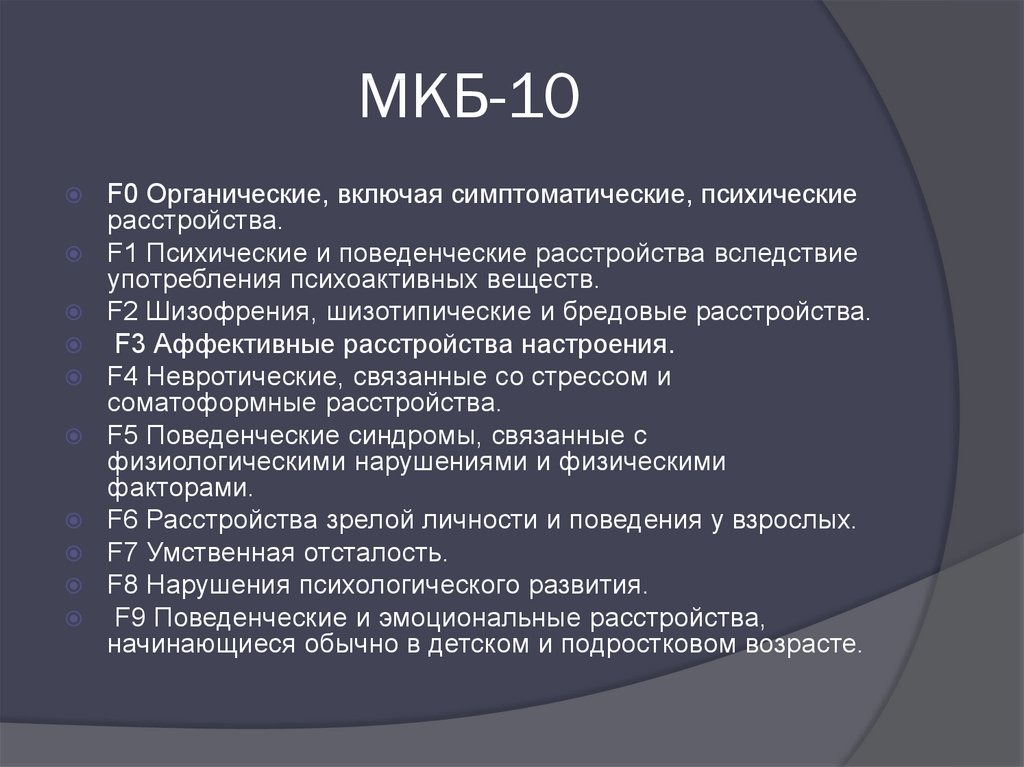

Код мкб 10 атерома головы

Код мкб 10 атерома головы 109 фото